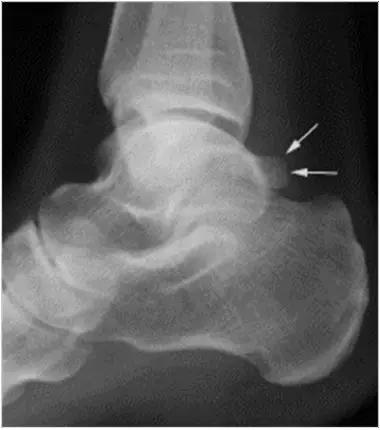

男,11岁,自述后踝下方疼痛,活动时为甚,并有一突起。

- 踝关节正侧位X 线平片,侧位片均显示距骨后方有三角形或椭圆形的距后三角骨。部分病例伴有轻度的踝关节骨性关节病。

- MRI 检查示距后三角骨及周围软组织有水肿信号,距后三角骨和距骨之间正常的低信号纤维连接中断,出现液性信号。

- 三角籽骨或距骨后三角结构模糊和变形,T1WI信号降低, T2WI信号升高,

- 周围脂肪水肿,

- 踇趾长屈肌腱信号升高,见鞘膜积液,

- 胫骨后下跟骨上缘骨结构形态变化和信号异常,

- 三角籽骨和距骨退行性囊变。

三角籽骨综合征

三角籽骨综合征并跟腱滑囊积液